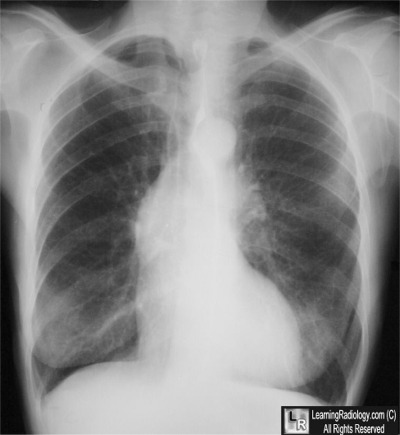

Case of the Week 552

What is the most likely diagnosis?

• 71 year-old with chest pain and syncope

Frontal Radiograph of Chest

3. Aortic Stenosis

Aortic Stenosis

• Most often as result of degeneration of bicuspid aortic valve

• Less commonly rheumatic heart disease or secondary to degeneration of a tricuspid aortic valve in person > 65